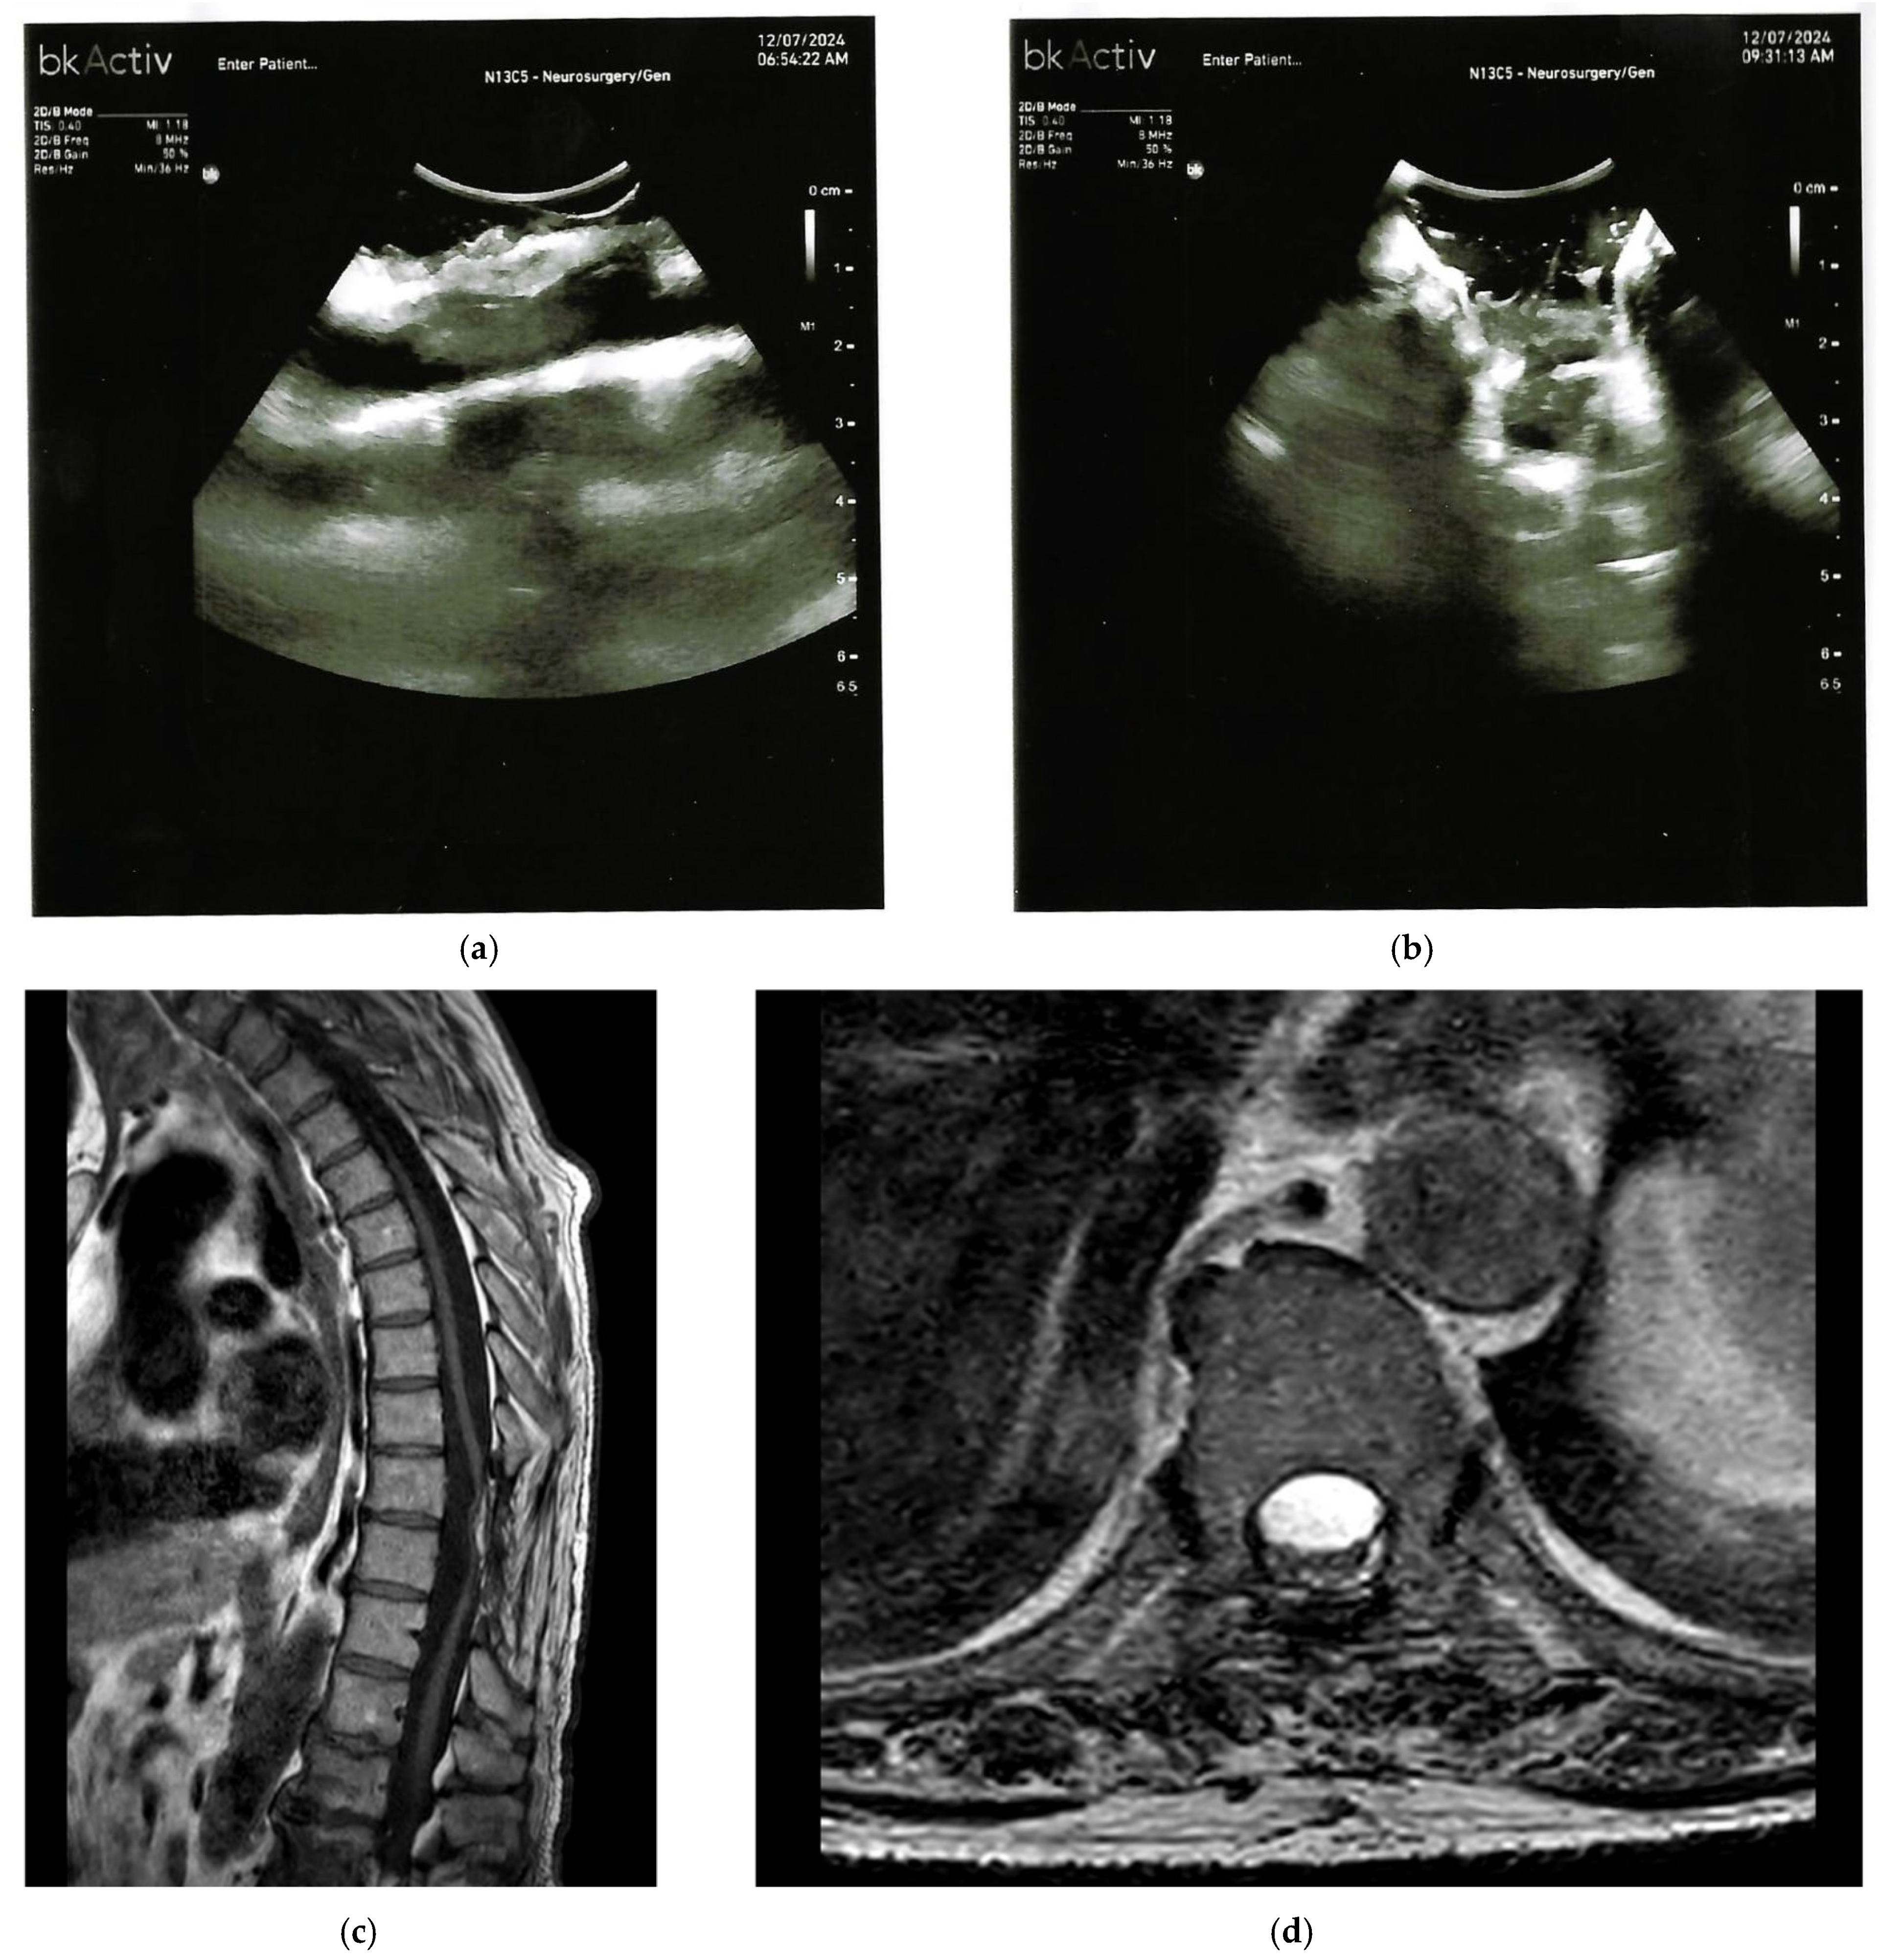

2. Disembryogenetic Cysts

| Neuroenteric or Respiratory Cysts | Well circumscribed, cerebrospinal fluid-like signal on T2; no enhancing solid component; focal cord compression. | Anechoic or hypoechoic cavity with well-defined margins, echogenic lining, occasional septations; eccentric cord displacement. |